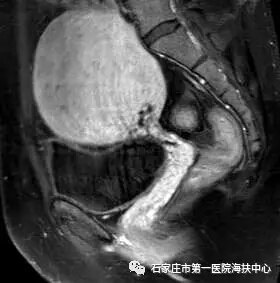

海扶术前磁共振图像